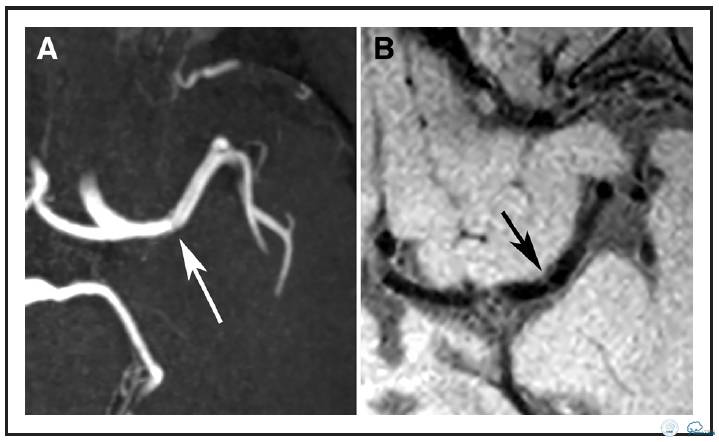

图3:64岁男性患者,左侧大脑中动脉(MCA)狭窄引起的左侧部分前循环梗死。A:TOF-MRA示左侧大脑中动脉(MCA)存在小的狭窄(白箭头)。B:横向的T1加权自旋回波采集容积重建图像上没有相应的血管壁病变。